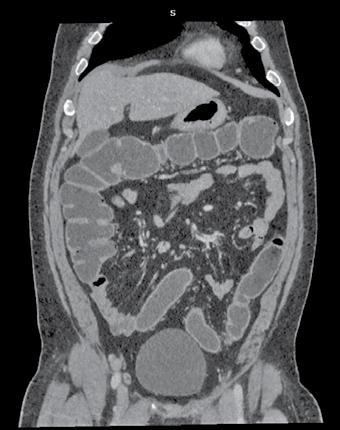

Rolul CT-ului în managementul cancerului rectal

Tomografia computerizată (CT) este una dintre primele investigații imagistice recomandate după confirmarea diagnosticului de cancer rectal. Aceasta poate oferi și unele informații despre invazia tumorală locală, dar rolul ei principal astăzi constă în evaluarea extensiei la distanță a bolii, fiind excelentă pentru identificarea metastazelor pulmonare și hepatice. CTul permite o evaluare rapidă și detaliată a cavității abdominale și toracice, având un rol cheie în stadializarea TNM (Tumor, Node, Metastasis) a cancerului.

Protocolul de examinare prin CT include utilizarea substanței de contrast intravenoase pe bază de Iod pentru a evidenția tumora primară și leziunile secundare. Examinarea durează, în general,

aproximativ 10-20 de minute, în funcție de complexitatea cazului și de necesitatea explorării mai multor regiuni anatomice. În mod uzual, în cadrul stadializării inițiale sunt evaluate toracele, abdomenul si pelvisul. De menționat că investigația CT este una iradiantă pentru pacient, raportul risc-beneficiu fiind totuși net în favoarea efectuării acesteia la pacienții diagnosticați cu cancer rectal.

Examinarea CT poate fi combinată cu tomografia cu emisie de pozitroni (PET), formând o tehnică de imagistică hibridă cunoscută sub numele de PET-CT. Aceasta presupune injectarea unui radiotrasor, de obicei fluorodeoxiglucoză (FDG), care se acumulează în zonele cu activitate metabolică crescută, tipică celulelor tumorale. Imagistica PET evidențiază aceste regiuni metabolice active, în timp ce CT-ul suprapus oferă detalii anatomice precise. PET-CT este o tehnică avansată, rezervată unor cazuri selectate, deosebit de utilă în stadializare în privința leziunilor secundare sau recidivei tumorale.

Metastaze pulmonare. Examen CT multislice, fereastră pulmonară, plan axial.

Din colecția Centrului de Imagistică, UMFCV